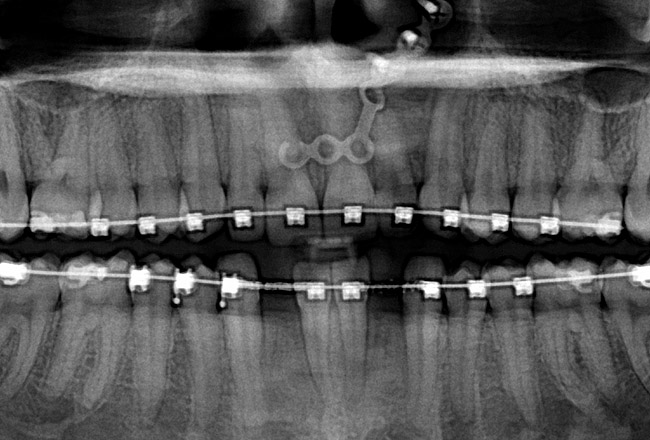

Fig 12 (and Fig 13). Incisors were too upright and had severe incisal wear. He was concerned about esthetics of the worn teeth and his insufficient lip support. Progress photo and panorex 9 months after corticotomies were performed on Nos. 6 through 11. Previous extraction sites were reopened orthodontically to improve function and fill lip support. Incisal edges were restored provisionally with composite resin. Note that despite the creation of adequate spaces to replace missing teeth, there is inadequate room for placement of dental implants because of severe tipping of all the anterior teeth. Osteotomy SFOT may have been a better choice because it would have allowed needed alveoloskeletal correction (without excessive tipping) instead of the primarily dentoalveolar correction common in corticotomy SFOT. Restorative dentist: Brad Jones, DDS.

Fig 13 (and Fig 12). Incisors were too upright and had severe incisal wear. He was concerned about esthetics of the worn teeth and his insufficient lip support. Progress photo and panorex 9 months after corticotomies were performed on Nos. 6 through 11.